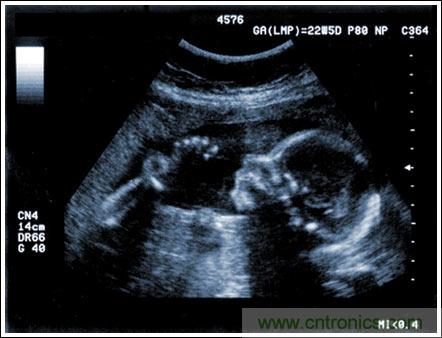

通過發(fā)射超聲能量進(jìn)入人體,接收并處理返回的反射信號,相控陣超聲系統(tǒng)可以生成體內(nèi)器官和結(jié)構(gòu)的圖像,映射血液流動和組織運動,同時提供高準(zhǔn)確度的血流速度信息。傳統(tǒng)設(shè)計中,構(gòu)建這樣的成像系統(tǒng)需要大量的高性能相控陣發(fā)射器和接收器,使得車載設(shè)備體積龐大且價格昂貴。近年來,隨著集成工藝的進(jìn)步,設(shè)計人員能夠獲得小尺寸、低成本而且高度便攜的成像系統(tǒng)方案,并可達(dá)到接近大型成像設(shè)備的性能指標(biāo)。而新的設(shè)計挑戰(zhàn)依然存在,即在進(jìn)一步提高方案集成度的同時提高系統(tǒng)性能和診斷能力。